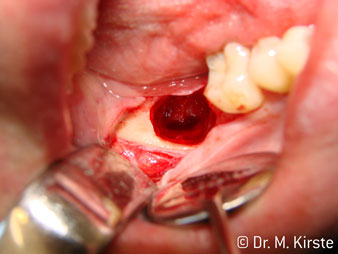

Угол 45° наконечника был выбран специально с учетом широкого круга преимуществ. Коллеги, которые работают в хирургии, и для которых этот наконечник был изначально создан, быстро оценят возможность эффективно работать в очень стесненном пространстве. В частности, при удалении зуба мудрости (рис. 2) не нужно сильно раздвигать мягкие ткани в области щеки (рис. 3). Конструкция головки наконечника в сочетании с небольшим поворотом головки во время препарирования позволяет быстро и безопасно выполнять работу в области задних коренных зубов.

Профессиональная конструкция подшипников внутри головки обеспечивает тихую работу бора; впечатляет атравматичное разделение зуба и корня (рис. 4-9).